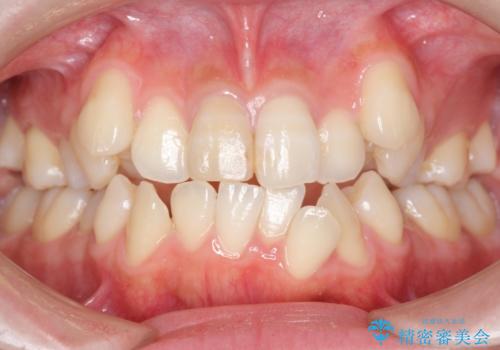

八重歯 前歯のがたがた 抜歯してワイヤー矯正

- 前歯のがたがたを主訴に来院。

八重歯と、前歯のやや開咬の症状もあり難易度としては中等度でした。

上下左右の小臼歯を抜歯し、ワイヤー矯正を行いました。